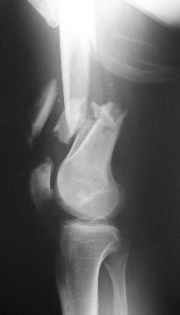

This is what we have done... As generally true for LISS look at the bone not the hardware.

There are two more srews above. The one not completely in got damaged head.